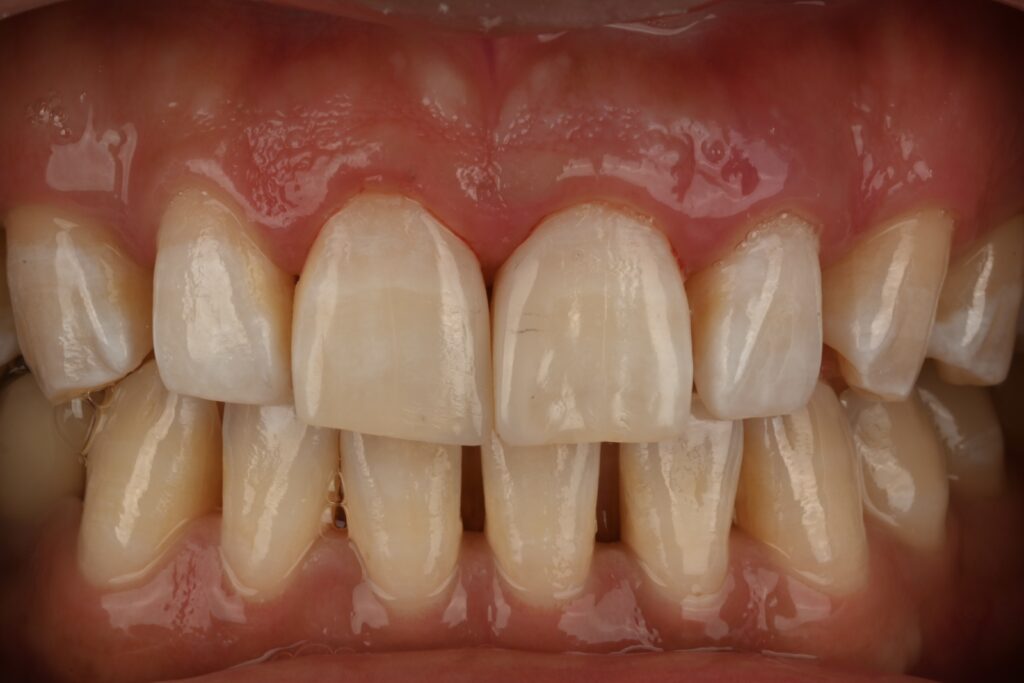

피니싱과 폴리싱을 마친 사진입니다

이제 점점 치아의 형태가 잡히는데요

추가적으로 광택을 더 내주면 안정적으로 치아의 외형이 잡힙니다

개인적으로 라미네이트보다 레진 바이오클리어 치아성형을 선호하는 이유는

간단합니다. 일단 치아삭제가 제로이며

재치료가 쉽고 파절에 강하며 훨씬 자연스럽기 때문입니다

그리고 잇몸의 건강에도 매우 좋게 친화적으로 치료가 가능합니다

치료후 사진만 봐도 안정적인걸 볼수 있습니다